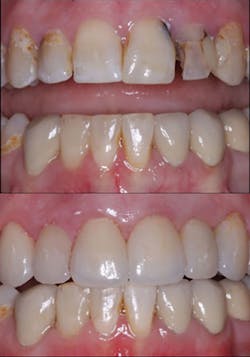

Figure 5: Although these six anterior teeth had significant facial caries and discoloration and required facial and proximal reduction, they had intact lingual surfaces. Veneers instead of crowns were planned for the patient.

Figure 6: The six anterior ceramic veneers on the teeth have served the patient well for several years.